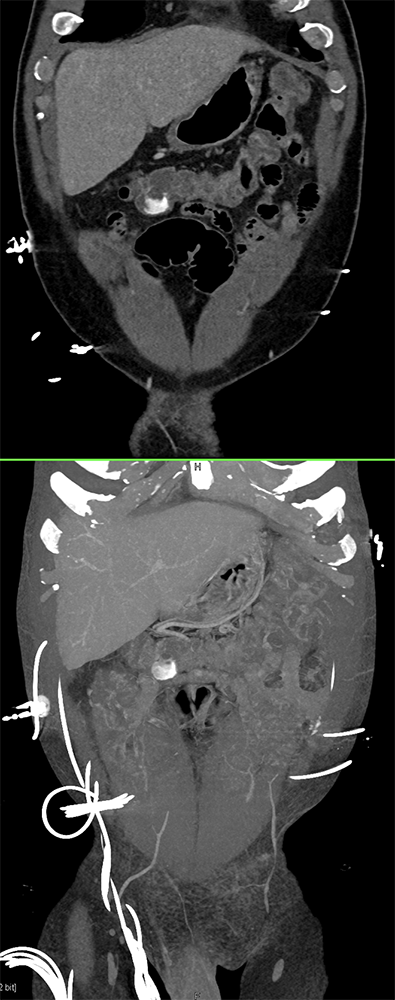

GIST Tumor Jejunum as the Cause of GI Bleeding ![]() |

![]() |

GI Bleed ![]() |